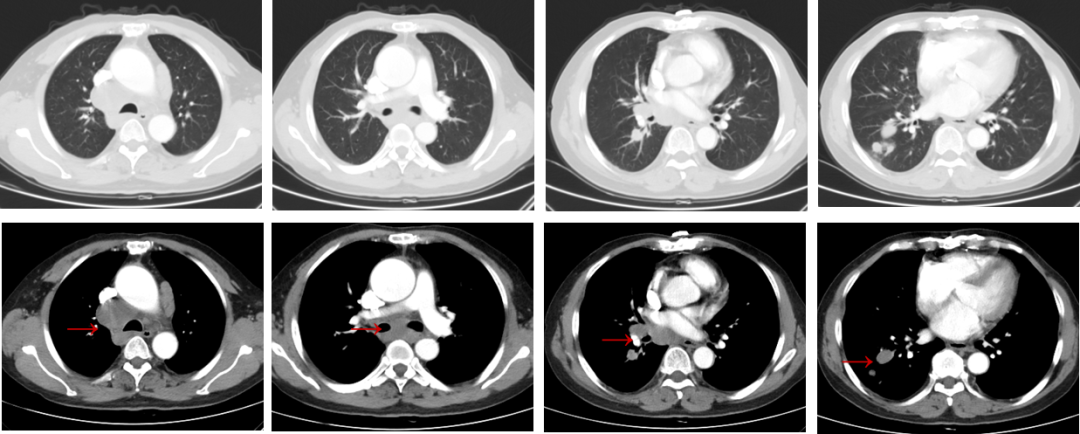

2020-11-03胸部CT:右肺下叶多发肿块及右肺门、纵隔淋巴结肿大,侵犯上腔静脉及肺血管。

图1.首诊胸部CT

图3.一线治疗后胸部CT结果